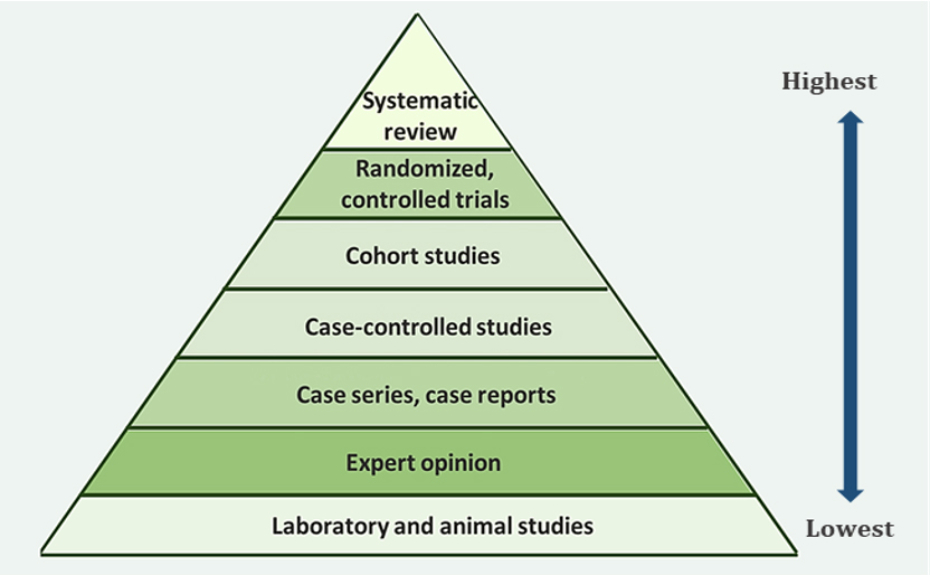

Usar odontología basada en la evidencia todos los días

La odontología basada en la evidencia (OBE) sirve para promover la salud bucal al brindar información basada en investigación, experiencia y las necesidades de cada paciente. Al ser parte del sector de la salud, es importante que siempre apliquemos la OBE para brindar los mejores cuidados que sea posible.